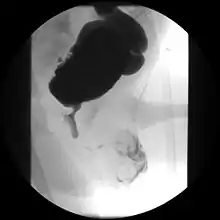

Cystourethrograph showing bladder obstruction with dilation of urethra and bladder

Ultrasound imaging can give information on the shape of the bladder, post-void residual volume, and evidence of kidney damage such as kidney size, thickness or ureteral dilation.[5] Trabeculated bladder on ultrasound indicates high risk of developing urinary tract abnormalities such as hydronephrosis and stones.[6] A voiding cystourethrography study uses contrast dye to obtain images of the bladder both when it is full and after urination which can show changes in bladder shape consistent with neurogenic bladder.[5]